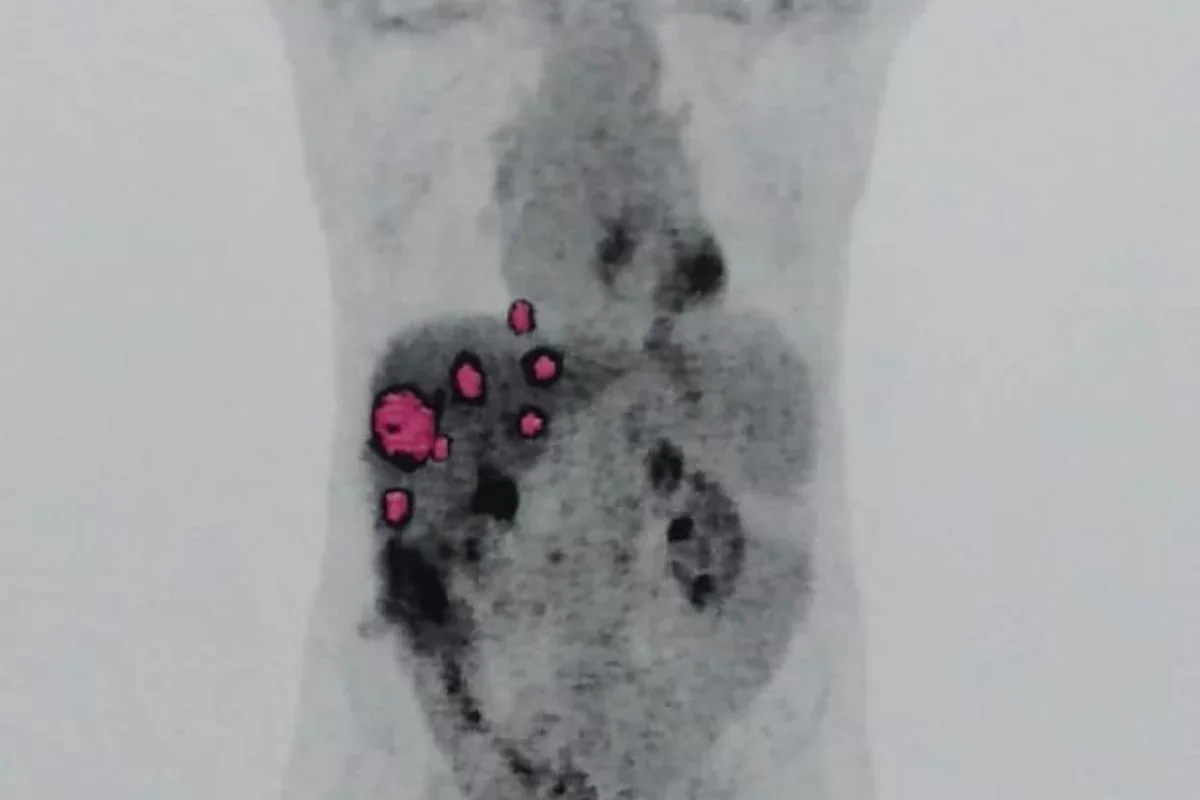

Um exame genético confirmou que o câncer que atinge Geraldo Vaz Junior, de 58 anos, teve origem no fígado que ele recebeu em um transplante feito em julho de 2023. A confirmação veio sete meses depois, quando, em março de 2024, foi descoberto um adenocarcinoma e um teste de DNA indicou que as células tumorais não pertencem ao organismo de Geraldo, mas sim ao doador do órgão.

A análise foi realizada no Hospital Albert Einstein, mesmo local onde o transplante foi feito e onde o paciente atualmente realiza quimioterapia. Em agosto do ano passado, médicos identificaram metástases nos pulmões de Geraldo. O laudo apontou que o tumor foi transmitido com o órgão, possivelmente por células isoladas ou micrometástases que só se manifestaram posteriormente.

A médica Caroline Daitx, especialista em medicina legal, avaliou os documentos e afirmou que o resultado do DNA é conclusivo. Segundo ela, o tumor apresenta cromossomos XX, típicos de uma mulher, enquanto Geraldo possui XY, o que comprova que o câncer veio da doadora do fígado. O Ministério da Saúde, inicialmente, negou relação entre o transplante e o câncer, mas depois reconheceu que os exames do doador não mostraram sinais de doença e que os protocolos foram seguidos.